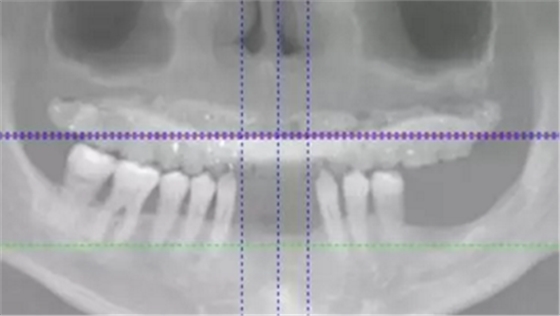

術(shù)后拍攝全景片。